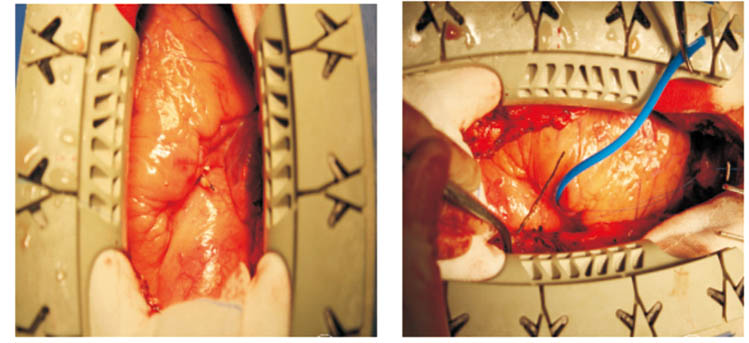

1 资料与方法患者男性,56岁。因间断活动后胸闷痛10余天入院。既往否认高血压、糖尿病,有长期吸烟史。患者近10余天于快速行走及劳累时出现心前区闷痛,无放散痛,无晕厥,休息后胸痛可自行缓解,近2天活动时胸痛频繁发作,且胸痛程度加重。本院门诊行超声心动图示左房38 mm,EF值66%,左室饱满,左室壁增厚,升主动脉稍宽,左室松弛性下降,门诊以“冠心病”收入院。入院查体:T 36.2 ℃,血压 159/84 mmHg(1 mmHg=0.133 kPa),一般状态尚可,呼吸平稳,口唇无发绀,胸壁皮肤无损伤,双肺未闻及啰音。心率62次/min,律齐,未闻及杂音。心电图示心率78 次/min,RV5>2.5 mV,心肌肥厚劳损;急诊肌钙蛋白I测定正常;急诊心肌酶CK-MB正常。入院初步诊断:急性冠脉综合征。入院第3天行冠脉造影示左右冠脉血管未见狭窄病变,透视下可见心包前壁一长约40 mm疑似金属条样物(图 1)。后行胸部CT血管三维成像见升主动脉前方可见条形高密度影,周围可见放射状伪影,长约5 cm,病变自右上至左下走行,于主动脉根部同右心室璧界限不清(图 2)。诊断:心脏异物。停用所有抗血栓药物,并转入我院胸外科治疗,转入胸外科1周后,在全麻下行“心脏异物清除术”,术中于主动脉根部前间壁、右冠开口旁2 cm,可见一长约0.5 cm金属条索样异物,通过主肺动脉窗刺入右心室流出道前壁心肌内,心表面无震颤,围绕异物刺入点,用4-0 prolene 线加垫片荷包缝合两圈,缓慢拔出金属异物,金属异物在心肌内长度约5.5 cm,测量金属条索样异物长度约6.0 cm,刺入点无出血,结扎荷包线(图 3)。术后诊断:心脏异物(金属丝)。追问病史,患者业余爱好舞鞭,该铁丝正是入院前10余天舞鞭时丢失的鞭子头端铁丝(鞭子梢)。术后手术切口愈合良好,术后第6天办理出院。

| 图 3 患者术中照片 |